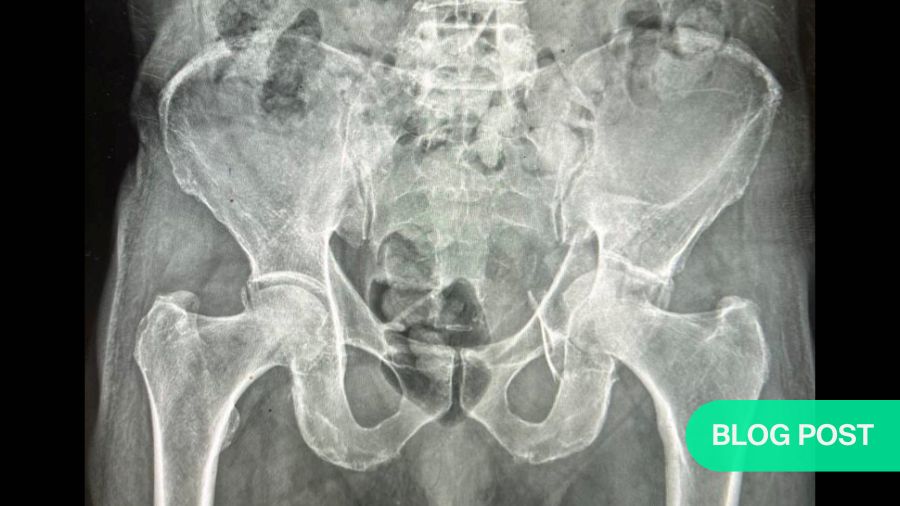

Pelvis and acetabulum

December 16, 2025Operative vs non-operative management of geriatric acetabular fractures: persisting clinical challenges in decision-making and outcome reporting

BY DR AHMED A. KHALIFA

November 24, 2025Sacral fractures: bridging spine and pelvic surgical expertise

BY DR ASHRAF N EL NAGA AND DR EMILIANO VIALLE